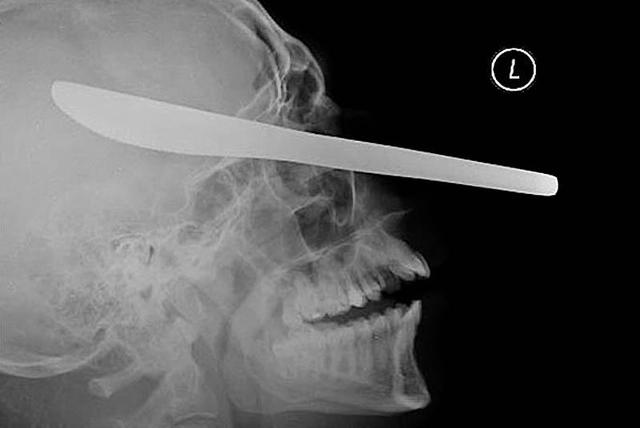

Нож в голове 10-летнего мальчика. Мальчик выжил.